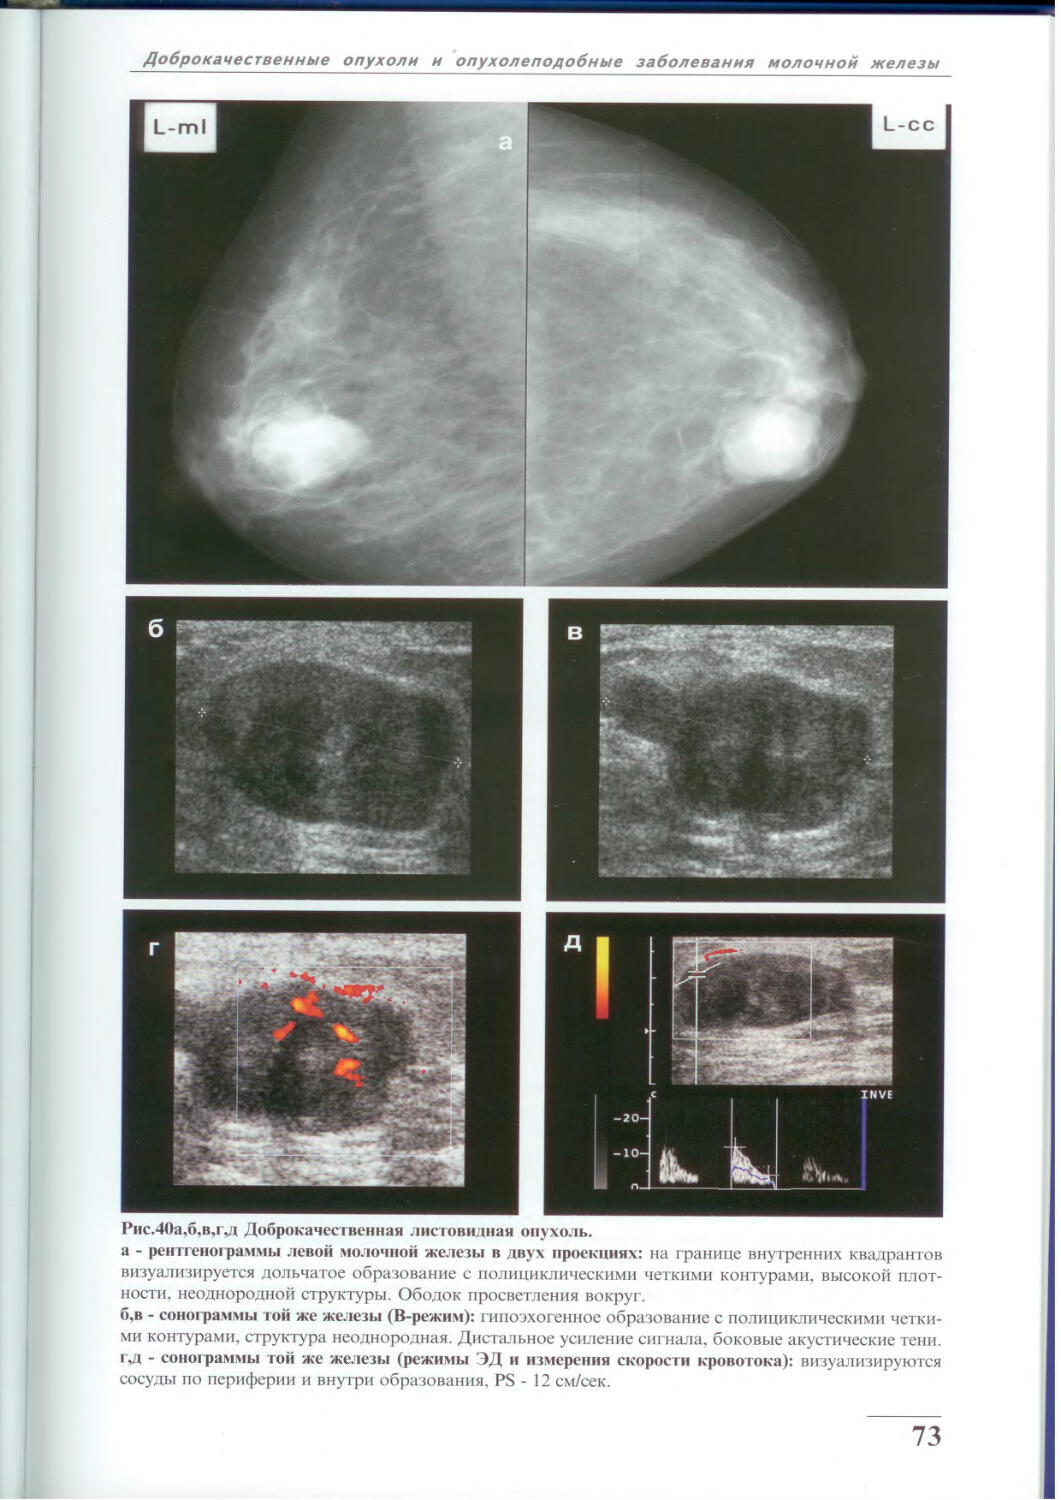

Фиброаденома молочной железы - доброкачественное образование, которое часто встречается у женщин. Оно может быть обнаружено при помощи различных методов диагностики, включая маммографию. Ниже представлены фотографии, помогающие понять, как выглядит данное заболевание.

Маммография и ее роль в диагностике фиброаденомы молочной железы

Маммография - это рентгенологическое исследование молочных желез. Оно позволяет выявить различные изменения в тканях, включая фиброаденому. На маммограммах можно увидеть структурные особенности опухоли и отследить ее динамику во времени.